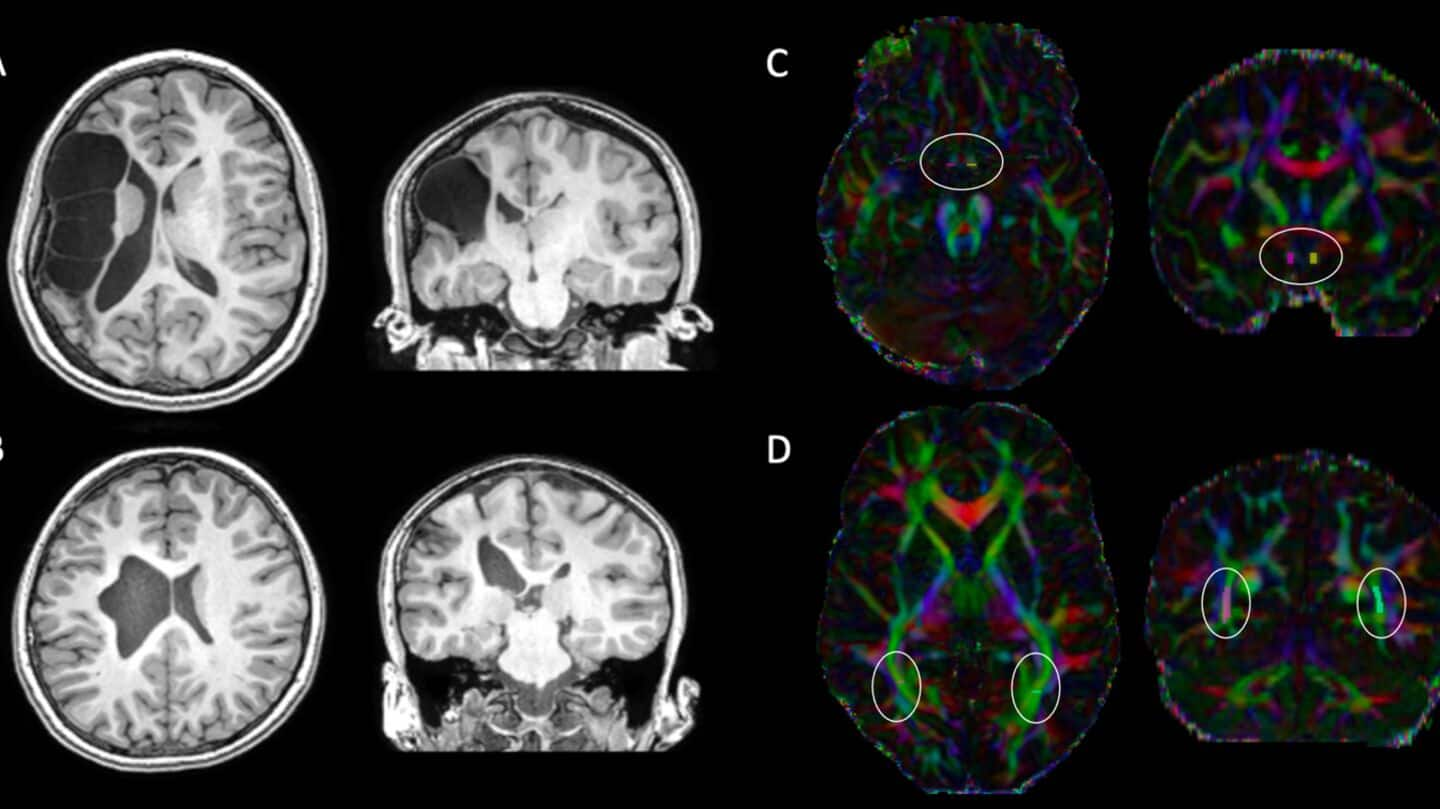

Scientists just mapped out how our brains change across our entire lives—breaking it down into five big stages.

They scanned over 3,800 people from newborns to age 90 and found key turning points at ages 9, 32, 66, and 83.